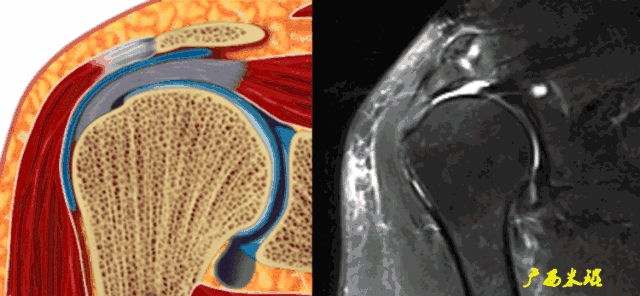

3、 肱二头肌长头腱病变

肱二头肌长头腱与肩袖关系极为密切,其肌腱炎、肌腱滑脱等改变很多情况下是伴随肩袖损伤而来的。当我们在MRI上发现肱二头肌长头腱的严重病变,应该也要考虑到有肩袖损伤的可能。

k、肱二头肌长头腱撕裂以及滑脱常常是肩袖撕裂的一种病理改变或者合并症,当我们看见这些改变,也应该认真的观察肩袖是否有撕裂。

4、肱二头肌长头腱伪影

肱二头肌长头腱有时与冈上肌因间隙而出现高信号条影,或者肱二头肌长头腱本身已经有退变信号,不仔细阅片时会误认为是冈上肌撕裂信号。